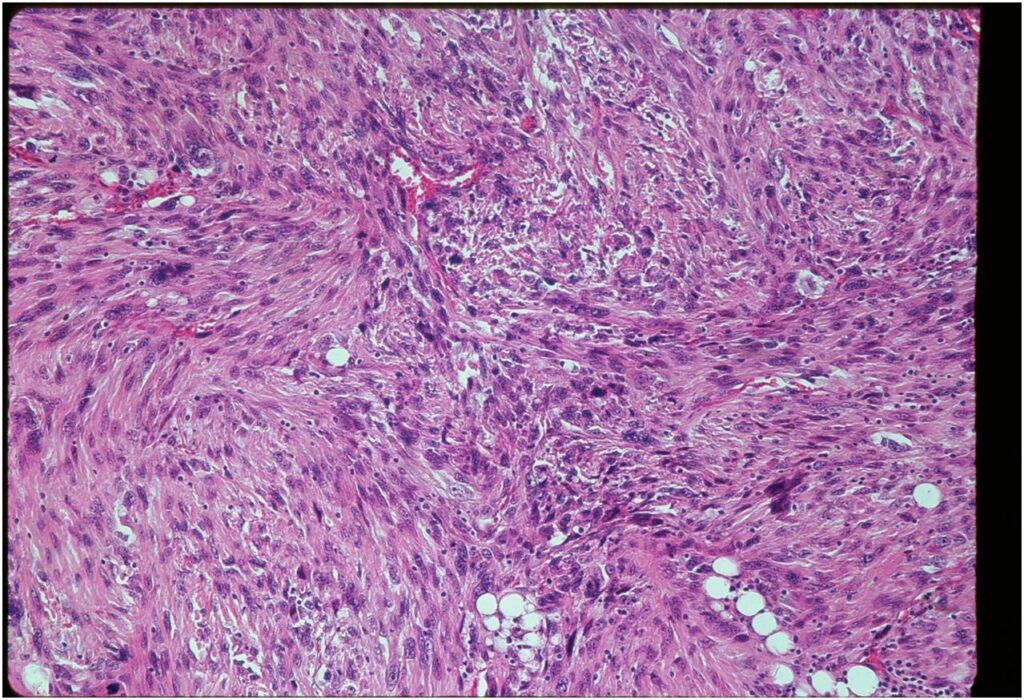

- Dedifferentiated component

- Predominant noncartilaginous/spindle sarcoma component varies

- Fibrosarcoma and MFH most frequently reported

- MFH is a high grade pleomorphic spindle cell tumor with a storiform pattern

- Osteosarcoma is third most common dedifferentiated component

- Rhabdomyosarcoma and angiosarcoma also reported

Junction of cartilaginous and noncartilaginous components is sharp and distinct. There are no dedifferentiated areas admixed in the middle of the cartilaginous areas

(Right Arrow) Spindle Cell Component